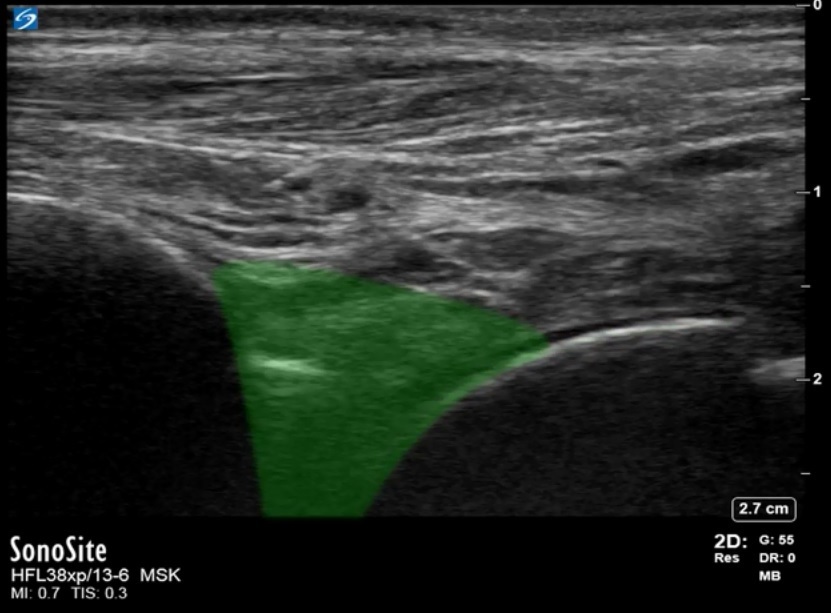

Bild: Fuß und Sprunggelenk, Recessus anterior des Tibiotalargelenks